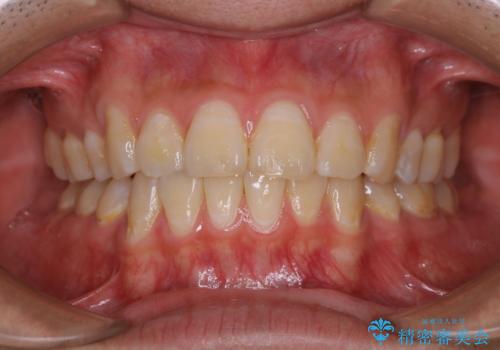

- 定期健診で全体的のチェックとクリーニング希望で来院されました。PMTC30分コースでクリーニングを行いました。

PMTCとは「Professional Mechanical Tooth Cleaning」の略で、専用の機器を使った歯のクリーニングです。

審美的面だけではなく、歯周病や虫歯・口臭などのリスクを予防することができます。

汚れを除去することにより、症状の早期発見につながります。